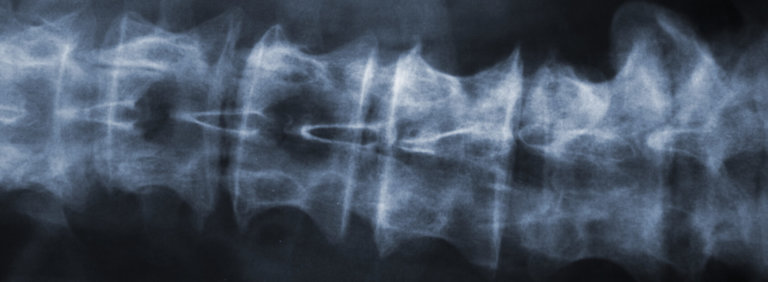

How We Diagnose Spondylolysis or Spondylolisthesis

Because patients with the small fractures of spondylolysis are sometimes asymptomatic, the fact that we see one on your X-ray does not mean it is the cause of your pain. For this reason, our doctors take great care to make a definitive diagnosis by:

- Examining your X-rays very carefully